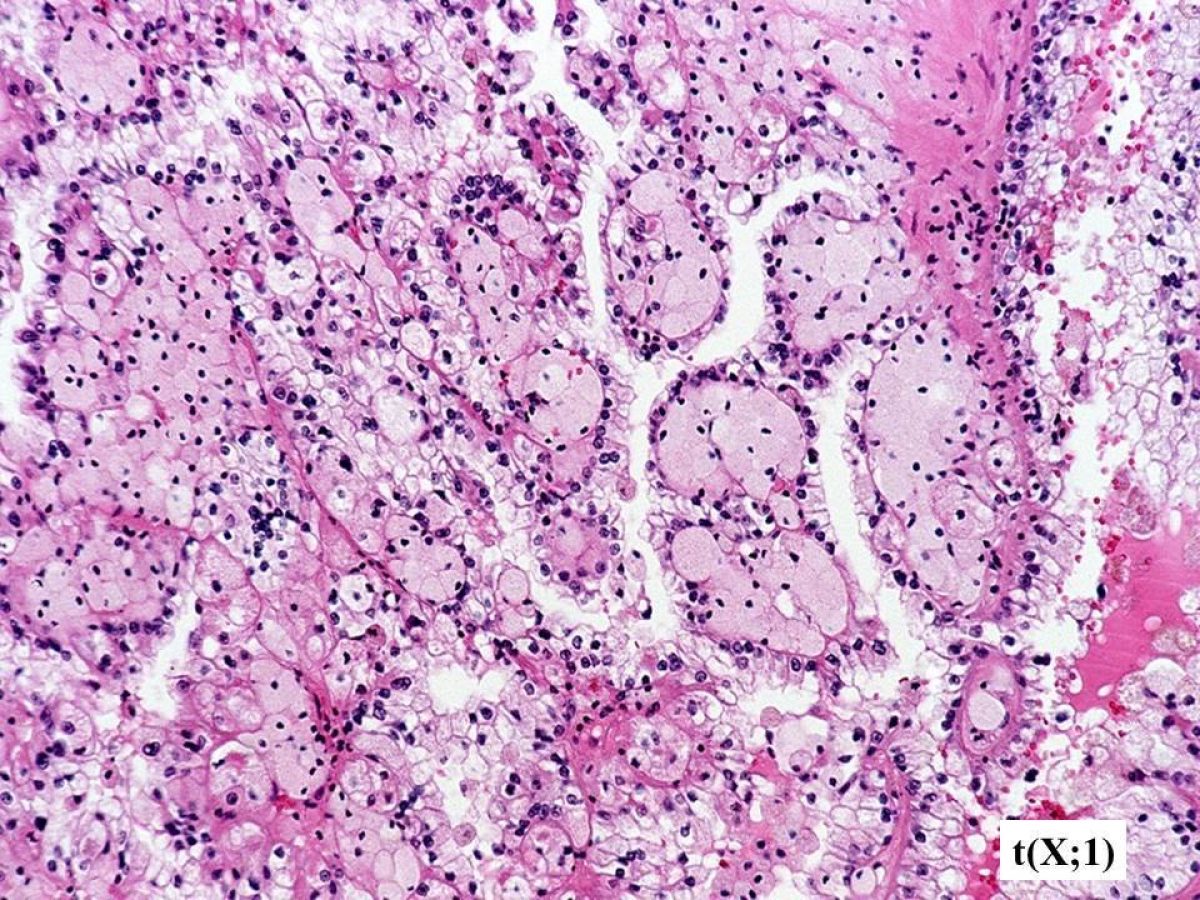

These pathology images are examples of what Translocation Renal Cell Carcinomas look like under the microscope.